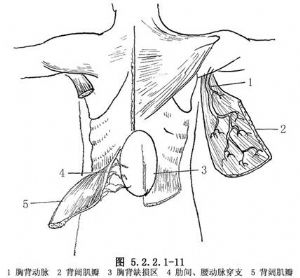

胸大肌瓣(pectoralis major muscle flaps):血運供應來自胸肩峯動脈和內乳動脈的肋間穿支,留其中之一即可保證血運。適於腋中線以前至胸骨處胸壁缺損,亦可用於胸腔內轉移肌瓣(圖5.2.2.1-10,5.2.2.1-11)。

背闊肌瓣(latissimus dorsi muscle flaps):血運主要由胸背動脈或肋間動脈和腰動脈穿支節段性供應。該肌瓣用於前側胸壁缺損重建。該肌瓣自根部切斷向後下反轉,保留動脈穿支,修補胸廓下部脊柱旁的胸壁缺損(圖5.2.2.1-10,5.2.2.1-11)。

腹直肌瓣(rectus abdominis muscle flaps):供應血管主要爲腹壁上血管。該肌瓣用於修復前胸壁和側胸壁缺損(圖5.2.2.1-10)。